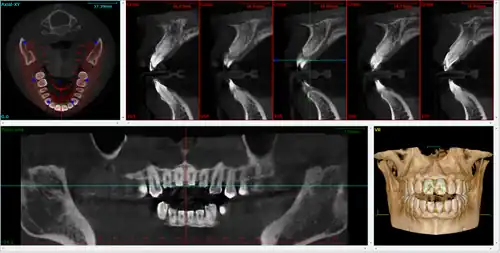

CBCT has become increasingly important in treatment planning and diagnosis in implant dentistry, ENT, orthopedics, and interventional radiology (IR), among other things. Perhaps because of the increased access to such technology, CBCT scanners are now finding many uses in dentistry, such as in the fields of oral surgery, endodontics and orthodontics. Integrated CBCT is also an important tool for patient positioning and verification in image-guided radiation therapy (IGRT).

During dental/orthodontic imaging, the CBCT scanner rotates around the patient's head, obtaining up to nearly 600 distinct images. For interventional radiology, the patient is positioned offset to the table so that the region of interest is centered in the field of view for the cone beam. A single 200 degree rotation over the region of interest acquires a volumetric data set. The scanning software collects the data and reconstructs it, producing what is termed a digital volume composed of three-dimensional voxels of anatomical data that can then be manipulated and visualized with specialized software.[2][3] CBCT shares many similarities with traditional (fan beam) CT however there are important differences, particularly for reconstruction. CBCT has been described as the gold standard for imaging the oral and maxillofacial area.

A dental cone beam scan offers useful information when it comes to the assessment and planning of surgical implants. The American Academy of Oral and Maxillofacial Radiology (AAOMR) suggests cone-beam CT as the preferred method for presurgical assessment of dental implant sites.[20]

As a 3D rendition, CBCT offers an undistorted view of the dentition that can be used to accurately visualize both erupted and non-erupted teeth, tooth root orientation and anomalous structures, that conventional 2D radiography cannot.[21]

Processing example using x-ray data from a tooth model:

algorithmic reconstruction

algorithmic reconstruction -

in-vivo image

in-vivo image